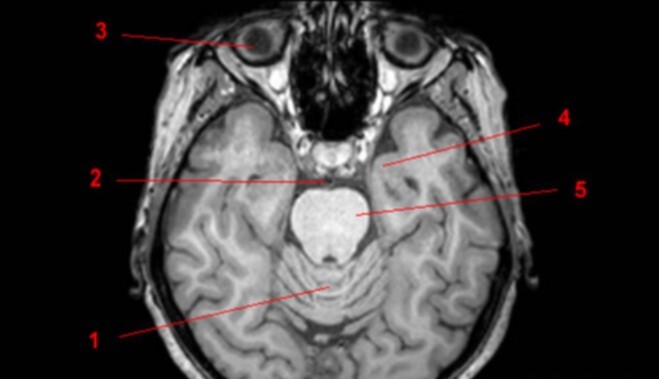

8

Label 1-5

A

1. Vermis of cerebellum

2. Basilar artery

3. Rt globe of eye

4. Lt temporal lobe

5. Pons